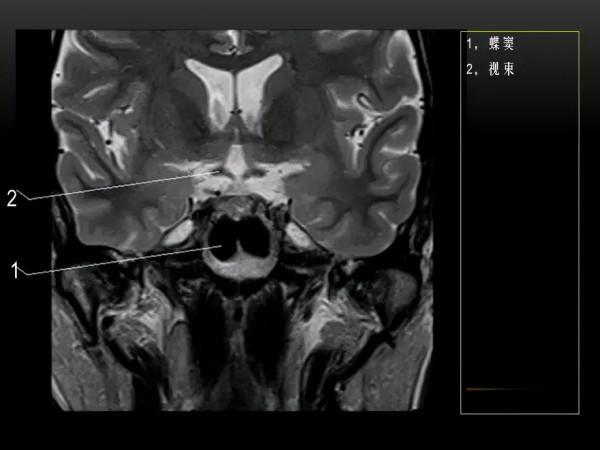

MRI下眼部及鼻竇的冠狀位解剖